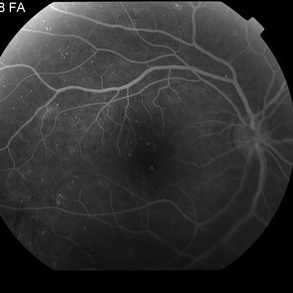

Proliferative Diabetic Retinopathy with Vitreous Hemorrhage - FA

Oct 18 2012 by Suber S. Huang, MD, MBA, FASRS

30 year old diabetic man with proliferative diabetic retinopathy and vitreous hemorrhage

Photographer: Stacie Hrvatin

Condition/keywords: cotton wool spots, neovascularization (NV), subhyaloid hemorrhage, vitreous hemorrhage